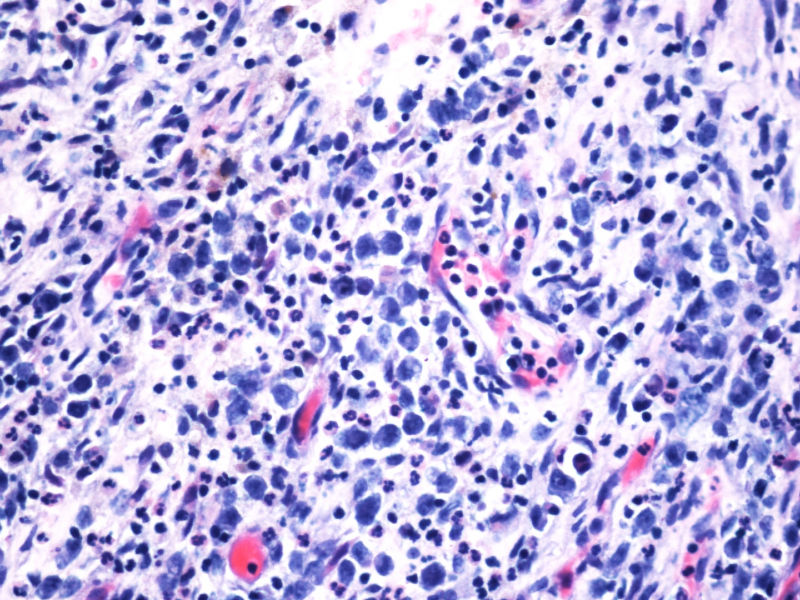

1. 支持CHL的方面: 本例CD15和D30,尤其是前者的表达强烈支持霍奇金淋巴瘤CHL,但似乎也不能完全排除ALCL;EMA-也支持CHL;

2. 支持ALCL的方面: 但CHL一般有更好的PAX5-表达;CHL的CD68一般不表达,而ALCL的KP1可以+但PGM1多-;CD3+细胞不多,可能是肿瘤细胞缺失了CD3的表达,如果再有CD5,CD4的结果就更好了;

3. 其他标记:如ALK, EBER, Oct-2, Bob-1, CD4,KP1,PGM1, ganzymeB, MUM1等对诊断也有帮助,另外也需考虑其他疾病。

本例CD68的表达也许很重要,HL可以有严重的炎症背景,但背景细胞是否会出现如此明显CD68阳性细胞,还请各位老师教我;而ALCL CD68大概可以阳性。另外就是哪些细胞是肿瘤细胞的问题了,可能未必局限于CD30阳性的大细胞吧。

的确如此,CD43不仅表达于多量T细胞淋巴瘤,还可以表达于一些B细胞淋巴瘤,如套细胞淋巴瘤、小淋巴细胞淋巴瘤/白血病、粒细胞肉瘤等等,甚至还可以表达于一些非肿瘤细胞。本例CD2,CD3,CD4,CD8,CD5,CD7均阴性,在这样的大细胞病变形态基础上,此时做CD43和细胞毒标记物只是寻找诊断ALCL的佐证,后来果然CD43和部分细胞毒标志物是阳性,对于“裸”免疫表型的ALCL,这一诊断思路也是WHO和许多文献推荐的,日常工作中也是我们也常常是这样做的。如果病变是在淋巴结内,HE是大细胞病变,且出现上述免疫表型,我想应该有许多病理医生就诊断了ALCL了。只是本例部位等临床特征特殊,诊断需要慎之又慎,但最后ALK-1也显示大细胞阳性,就增加了诊断的信心。